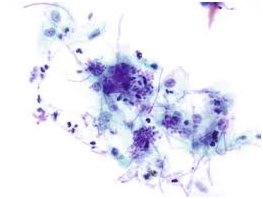

Figure 1 Candida pseudohyphae and yeast forms with inflammatory cells- aspiration cytology.

Acute candidiasis: The distinguishing aspect is the presence of neutrophils in the stratum corneum. Disseminated disease expounds dermo-epidermal inflammatory infiltrate with intra-epithelial micro-abscesses.1,5 Fungal components are infrequent. Periodic acid Schiff(PAS), Silver Methanamine (Grocott stain- black fungal hyphae with a green environment and is specific for the deteriorating fungus ) aids in delineating the organism.1,5